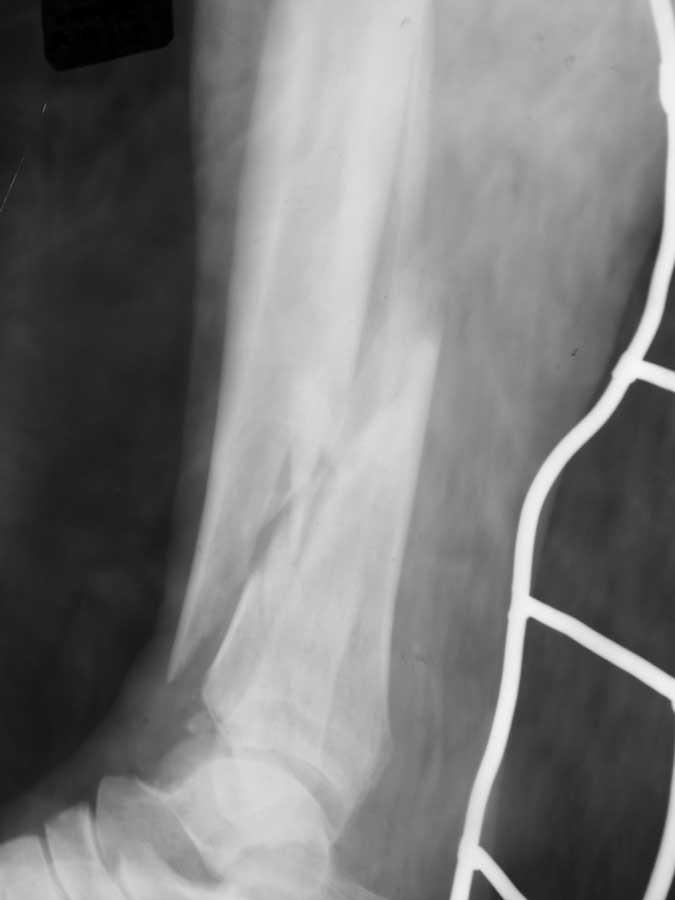

[Ortho] открытый перелом н/3 обеих костей левой глени

рентгенограммы

Имя     : 100_0375[1].JPG

Тип     : image/jpg